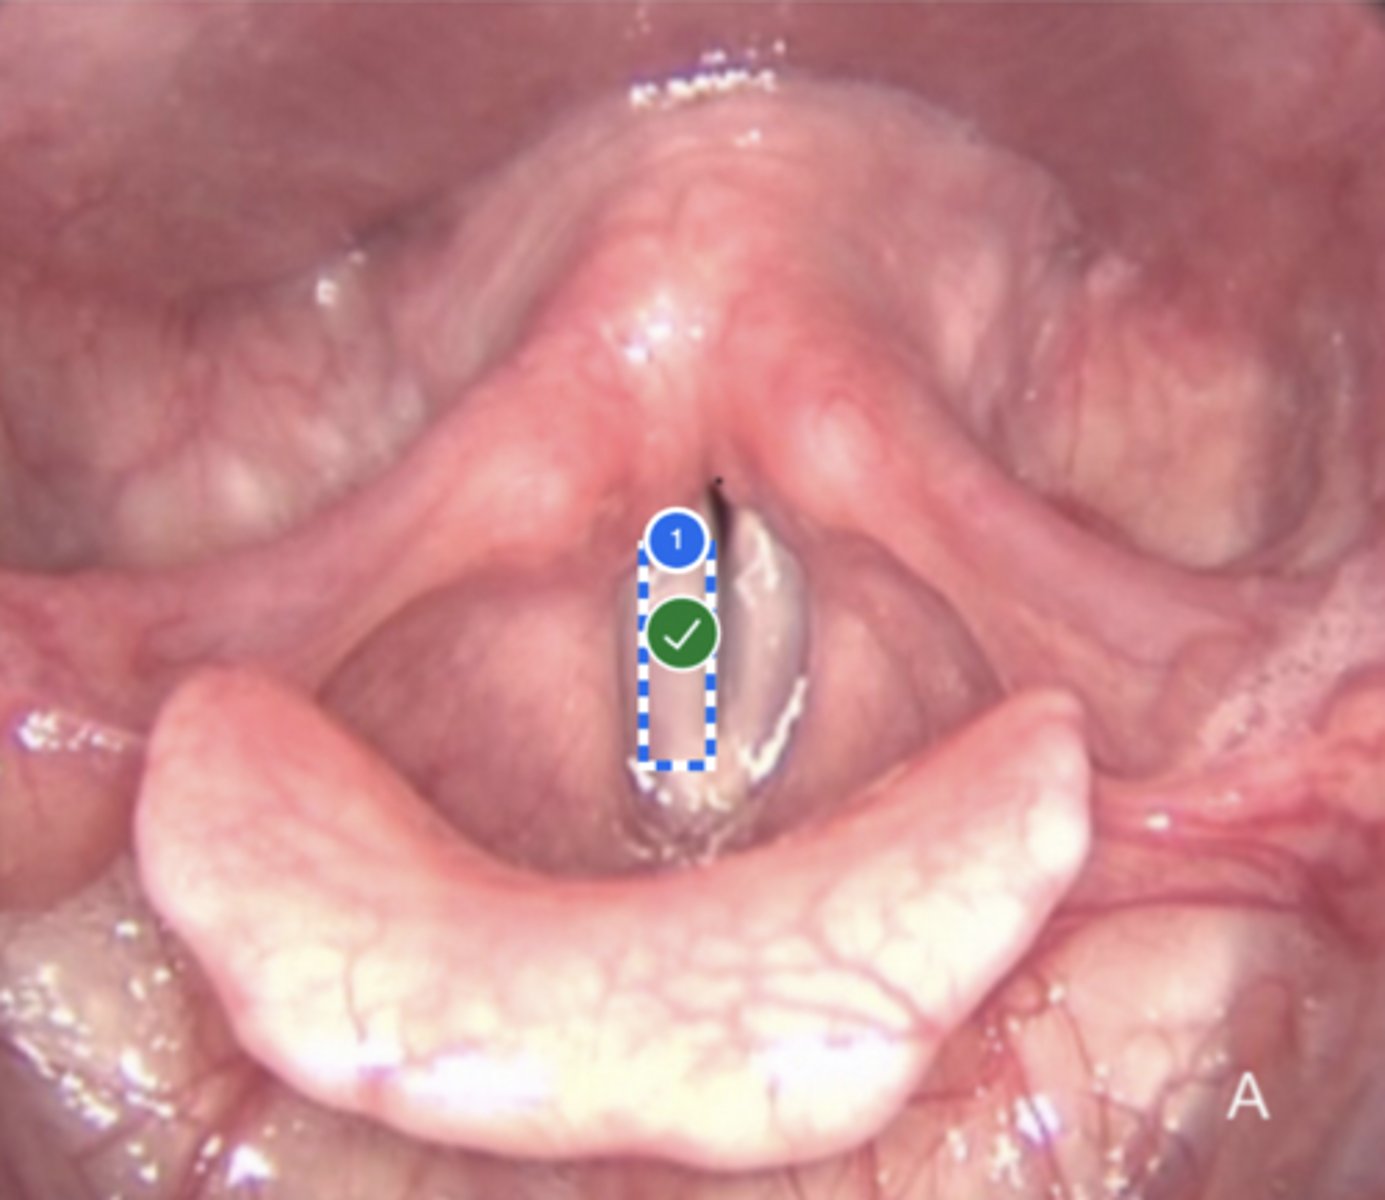

Label left true vocal fold (superior view)

Label right false vocal fold (superior view)

label right arytenoid (superior view)

Label trachea (superior view)

Label epiglottis (superior view)

Label left aryepiglottic fold (superior view)

Label laryngral surface of epiglottis (superior view)

Label lingual surface of epiglottis (superior view)

Label base of tongue (superior view)

Label right pyriform sinus (superior view)

Label upper esophageal sphincter (superior view)

Label right true vf (superior view)